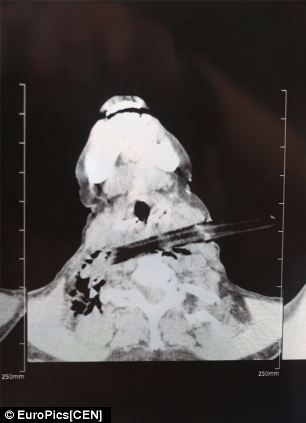

| Hình ảnh chụp X-quang cho thấy nhánh cây đâm sâu vào cổ bà Tô Lệ Dư. Ảnh: CEN |

Bác sĩ Vịnh Trương – người phẫu thuật cho bà Tô - cho biết: “Vật thể không làm tổn thương các cơ quan quan trọng ở cổ. Bà ấy là người phụ nữ may mắn và dũng cảm”.